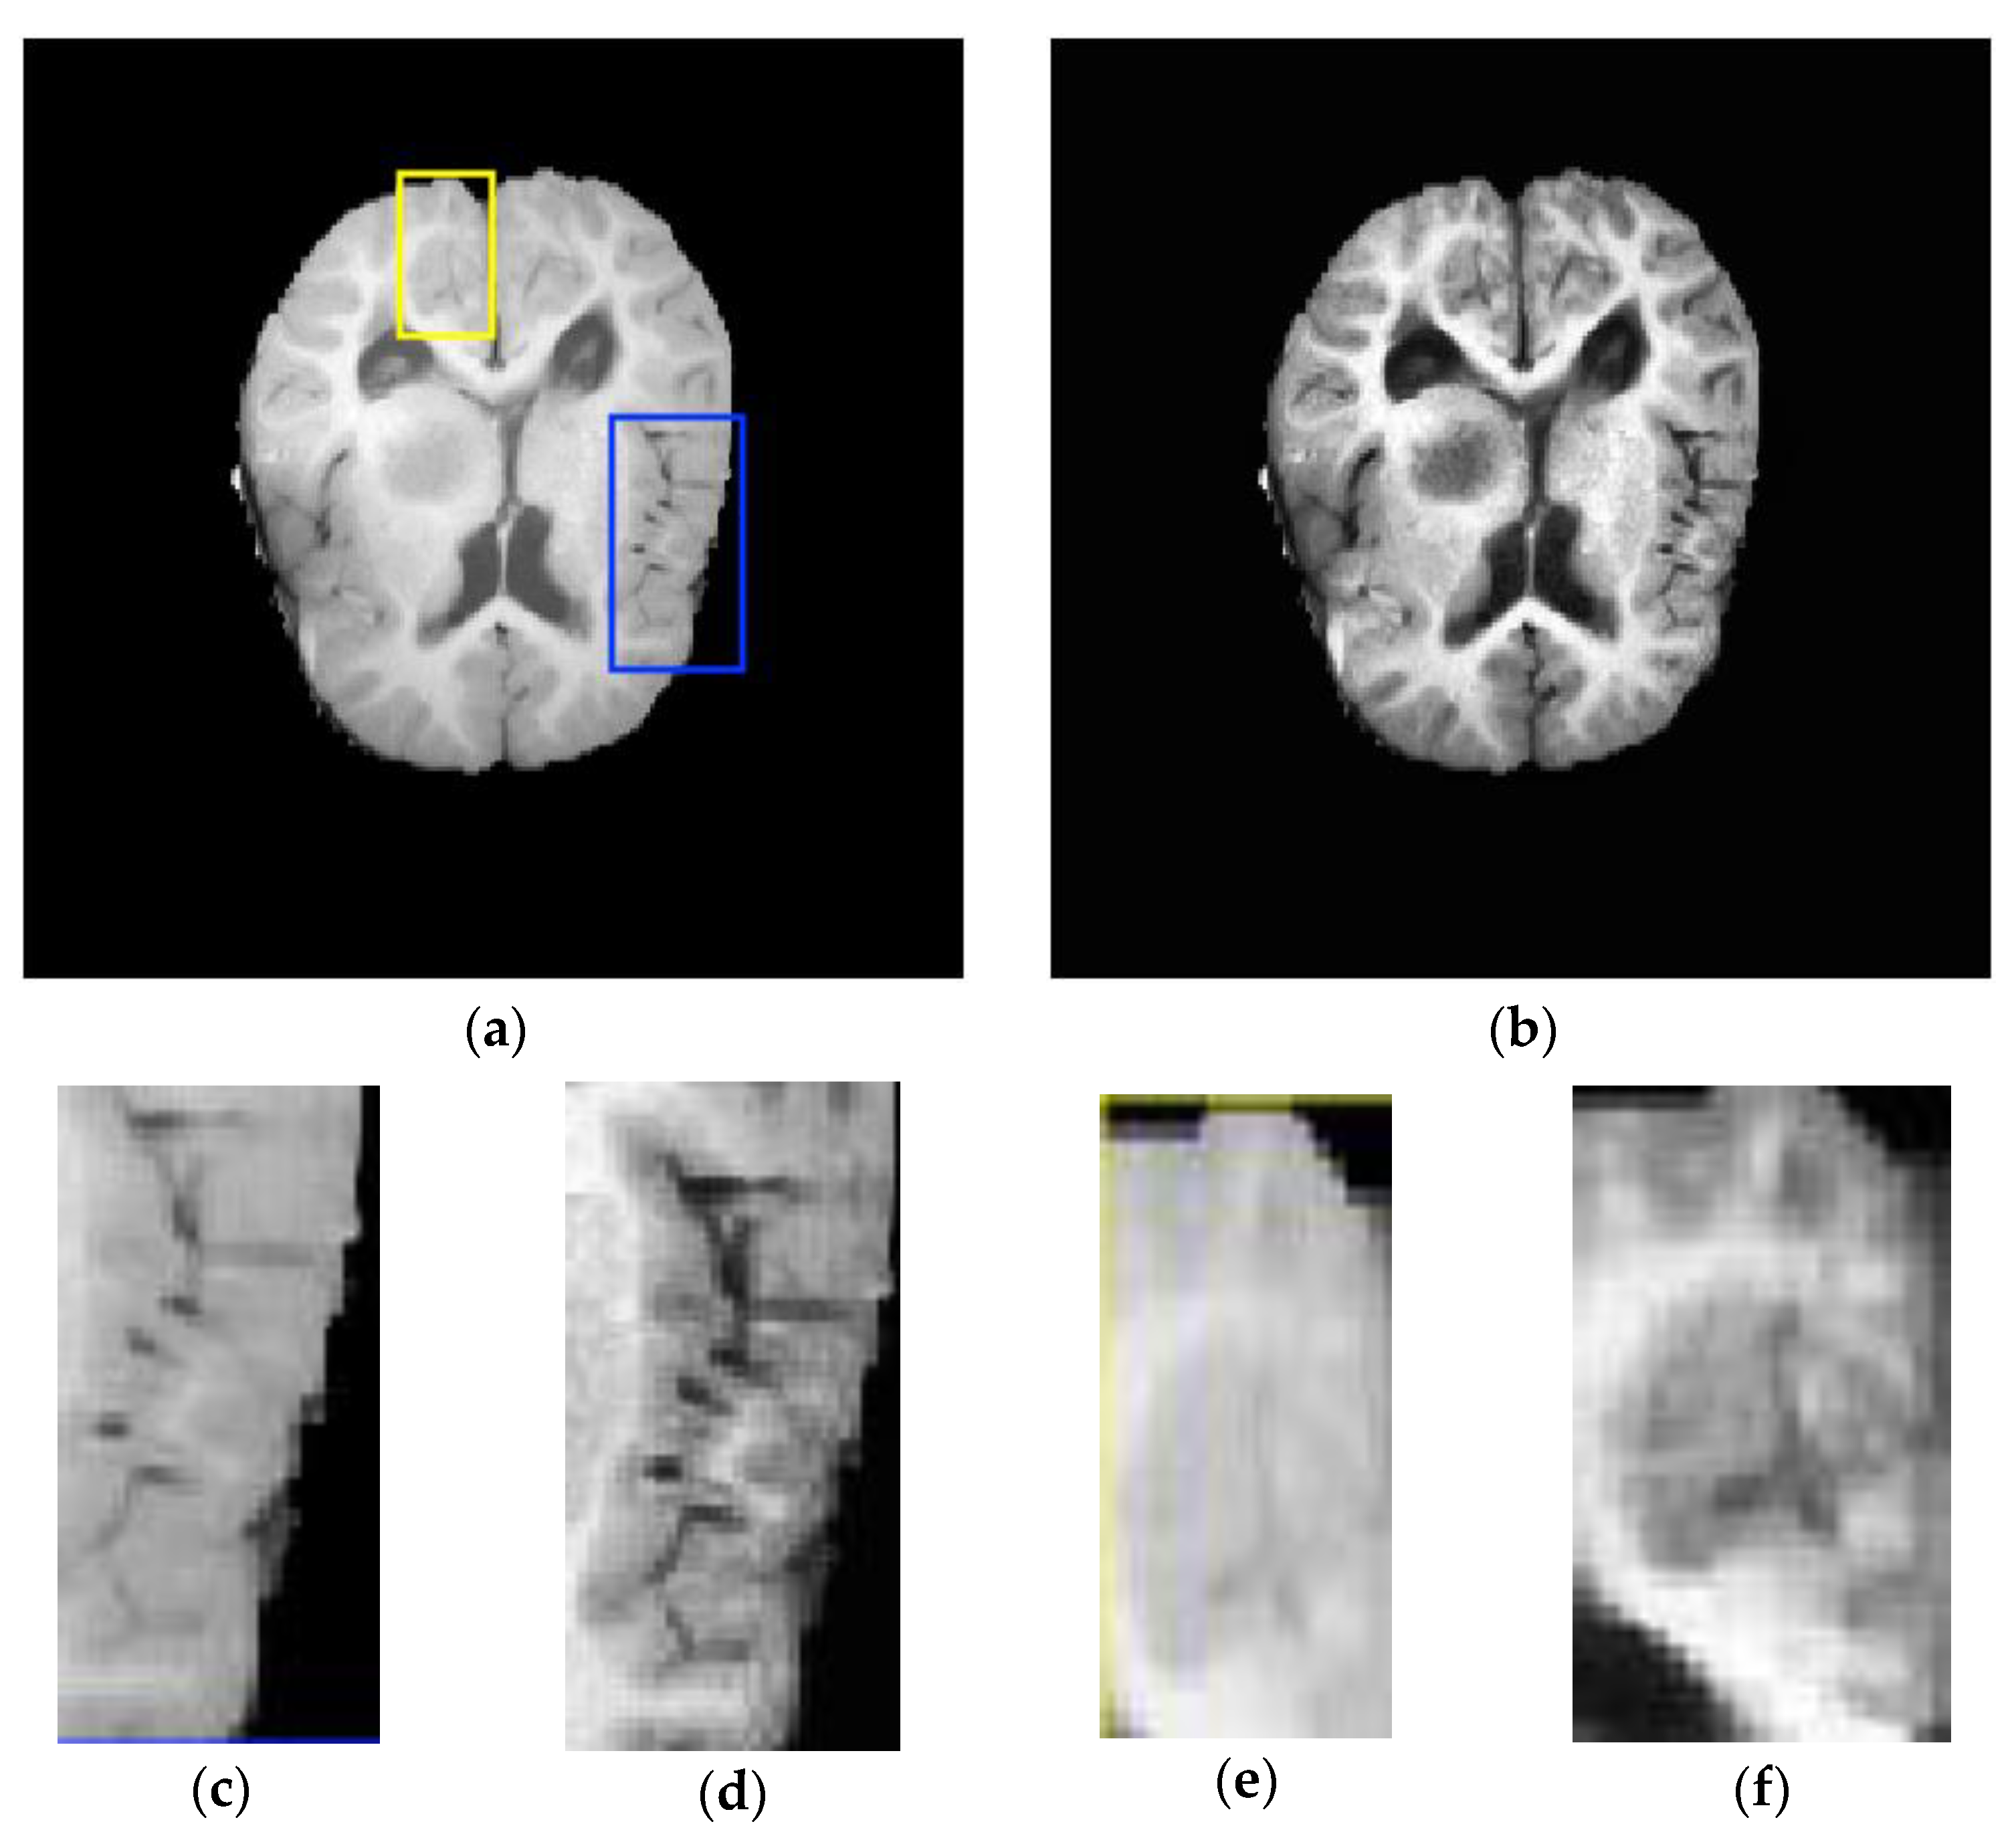

- Intensity inhomogeneity: This is due to the intensity of non-homogeneity of homogeneous tissues during contrast injection and the variations of spatial intensity over each dimension.

- Bias field: The bias field is another challenge faced during the process of brain segmentation in MR images, which is caused by the defects in the acquisition sequences or radiofrequency coil imperfections. The various biases associated with MR images include shading, noise, artifacts, and partial volume effects.

- Non-standardized intensity: The intensity of MR modalities depends on the magnetic fields and radio wave parameters, which are, in turn, influenced by the MR system hardware requirements.